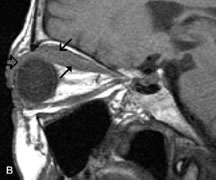

On MRI, uveal melanomas have a typical appearance that helps to differentiate them from other primary and secondary intraocular tumors as well as choroidal detachments. Pigmented melanomas are hyperintense on Tl-weighted images, hypointense on T2-weighted studies, and hyperintense on proton density–weighted examinations (Fig. 24).30,31,50,80–82 These signal characteristics have been attributed to the paramagnetic properties of melanin because of stable free radicals that shorten the T1 and T2 relaxation times. Moderate enhancement is seen on postgadolinium T2-weighted images. Gadolinium-enhanced T1-weighted images are particularly sensitive in detecting choroidal melanomas.83 MRI may be less sensitive in detecting extrascleral extension of tumor than echography performed by an experienced ultrasonographer.84

Fig. 24. A. T1- and (B) T2-weighted MR scans demonstrate a small nodular intraocular mass (arrows) that is very hyperintense on the T1-weighted scan and hypointense on the T2-weighted image. This signal intensity pattern is due to the presence of free radicals within melanin granules. C and D. Postcontrast fat-suppressed T1-weighted scans demonstrate homogeneous intense enhancement of the lesion and no evidence of seleral penetration or optic nerve invasion.